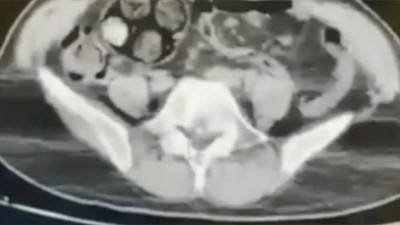

Bayburt’ta uyuşturucuyu ticareti yaptığı şüphesiyle yakalanan İran uyruklu şahsın mide ve bağırsaklarından 588,55 gr metamfetamin çıkarıldı. Şahıs...